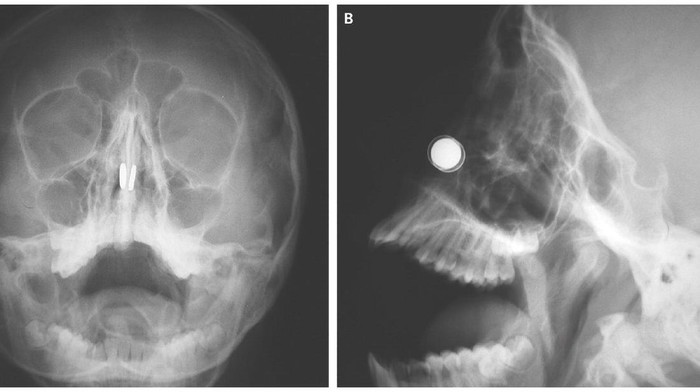

5. Hidung rusak karena magnet mainan

Ia akhirnya dibawa ke rumah sakit dan hasil rontgen melihat magnet menjepit bagian dinding hidung yang memisahkan lubang hidung kiri dengan kanan. Awalnya dokter mencoba memisahkan kedua magnet tersebut dari luar namun gagal. Pada akhirnya dokter berhasil mengangkat magnet tersebut dengan menggunakan bantuan magnet lain. Lapisan dinding hidungnya mengalami kerusakan cukup parah yang membuat tulang rawan di dalamnya terekspos. Bila dibiarkan lebih lama bisa terjadi kematian jaringan membuat dinding hidung jadi bolong.

Dokter pun memberi lapisan khusus kepada anak itu untuk melindungi dinding hidungnya dan setelah enam bulan kemudian ia dilaporkan bisa pulih kembali.